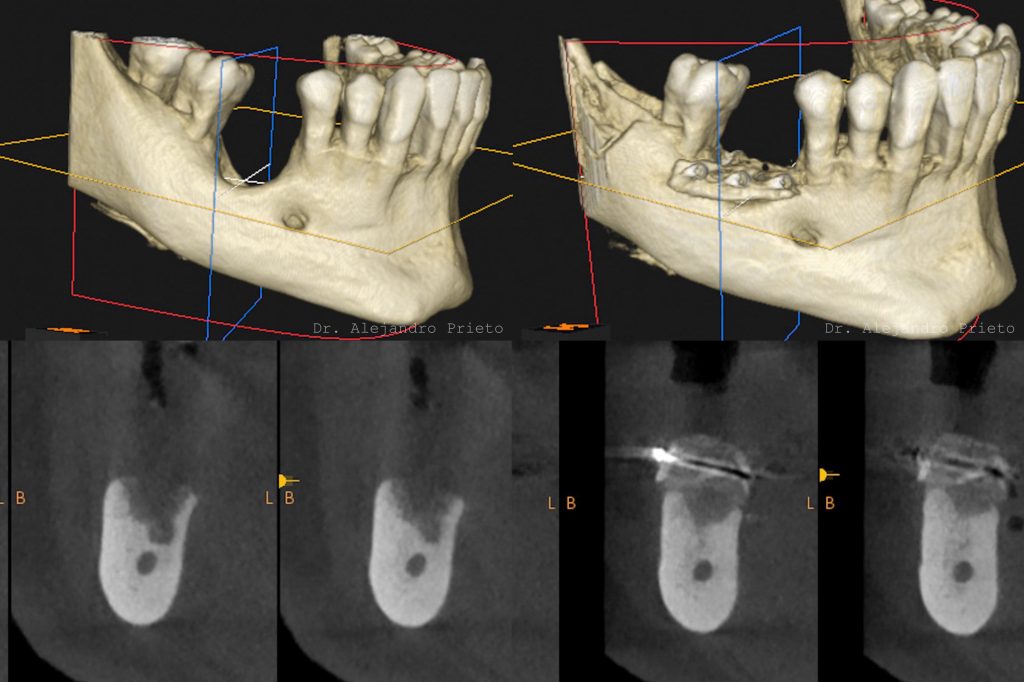

1. Estudio inicial con TAC 3D

Se analiza la cantidad y calidad del hueso para determinar la técnica de injerto más adecuada y planificar el procedimiento con precisión.

En todos los casos, un estudio inicial con TAC 3D es imprescindible para determinar la viabilidad del injerto y elegir la técnica más segura y eficaz.